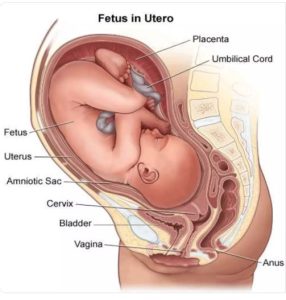

Mu gikorwa cy’ibyara, hari imyanya myibarukiro igira uruhare rukomeye mu gutuma umwana avuka neza. Iyo myanya ni nyababyeyi, umuyoboro w’inda, n’uruhago, ndetse n’ibindi bice bifasha mu gutwara no gusohora umwana. Ibi bice byose bikorana mu buryo bwihariye kugira ngo ibyara bigende neza.

Nyababyeyi (Uterus)

Ni igice gikomeye giherereye imbere mu nda, aho umwana aba ari mu mutekano mu gihe cyose umubyeyi atwite. Nyababyeyi iha intungamubiri n’umwuka binyuze mu ngobyi (placenta ) ikanamuha urwinyagamburiro rwo gukuriramo neza. Iyo igihe cyo kubyara kigeze, nyababyeyi ni yo isunika umwana kugira ngo avuke.

Inkondo y’umura (Cervix)

Ni igice gihuza nyababyeyi n’inzira y’umwana asohokeramo. Mu gihe cyo kubyara, inkondo y’umura igenda yaguka buhoro buhoro kugira ngo umwana abone aho anyura. Iyo itaguka neza, kubyara biragorana.

Inzira y’umwana asohokeramo (Vagina)

Ni inzira umwana anyuramo agiye kuvuka. Ni igice kigomba kuba cyoroshye kandi gifite imbaraga zo kwaguka kugira ngo umwana asohoke neza.

Ingobyi ( placenta)

Ni urutiriro rw’inda rufasha umwana kubona amaraso, intungamubiri, n’umwuka. Placenta ikunze kwifata ku rukuta rw’inyababyeyi (uterine wall), cyane cyane mu gice cyo hejuru cy’inyababyeyi (fundus) cyangwa inyuma (posterior wall). Aha ni ho haba amaraso menshi, bikayiha ubushobozi bwo guha umwana ibiryo n’umwuka.

Kuba placenta ikunze kwifata hejuru cyangwa inyuma bituma inzira y’umwana (inkondo y’umura) idahagarikwa, bityo kubyara bikagenda neza.